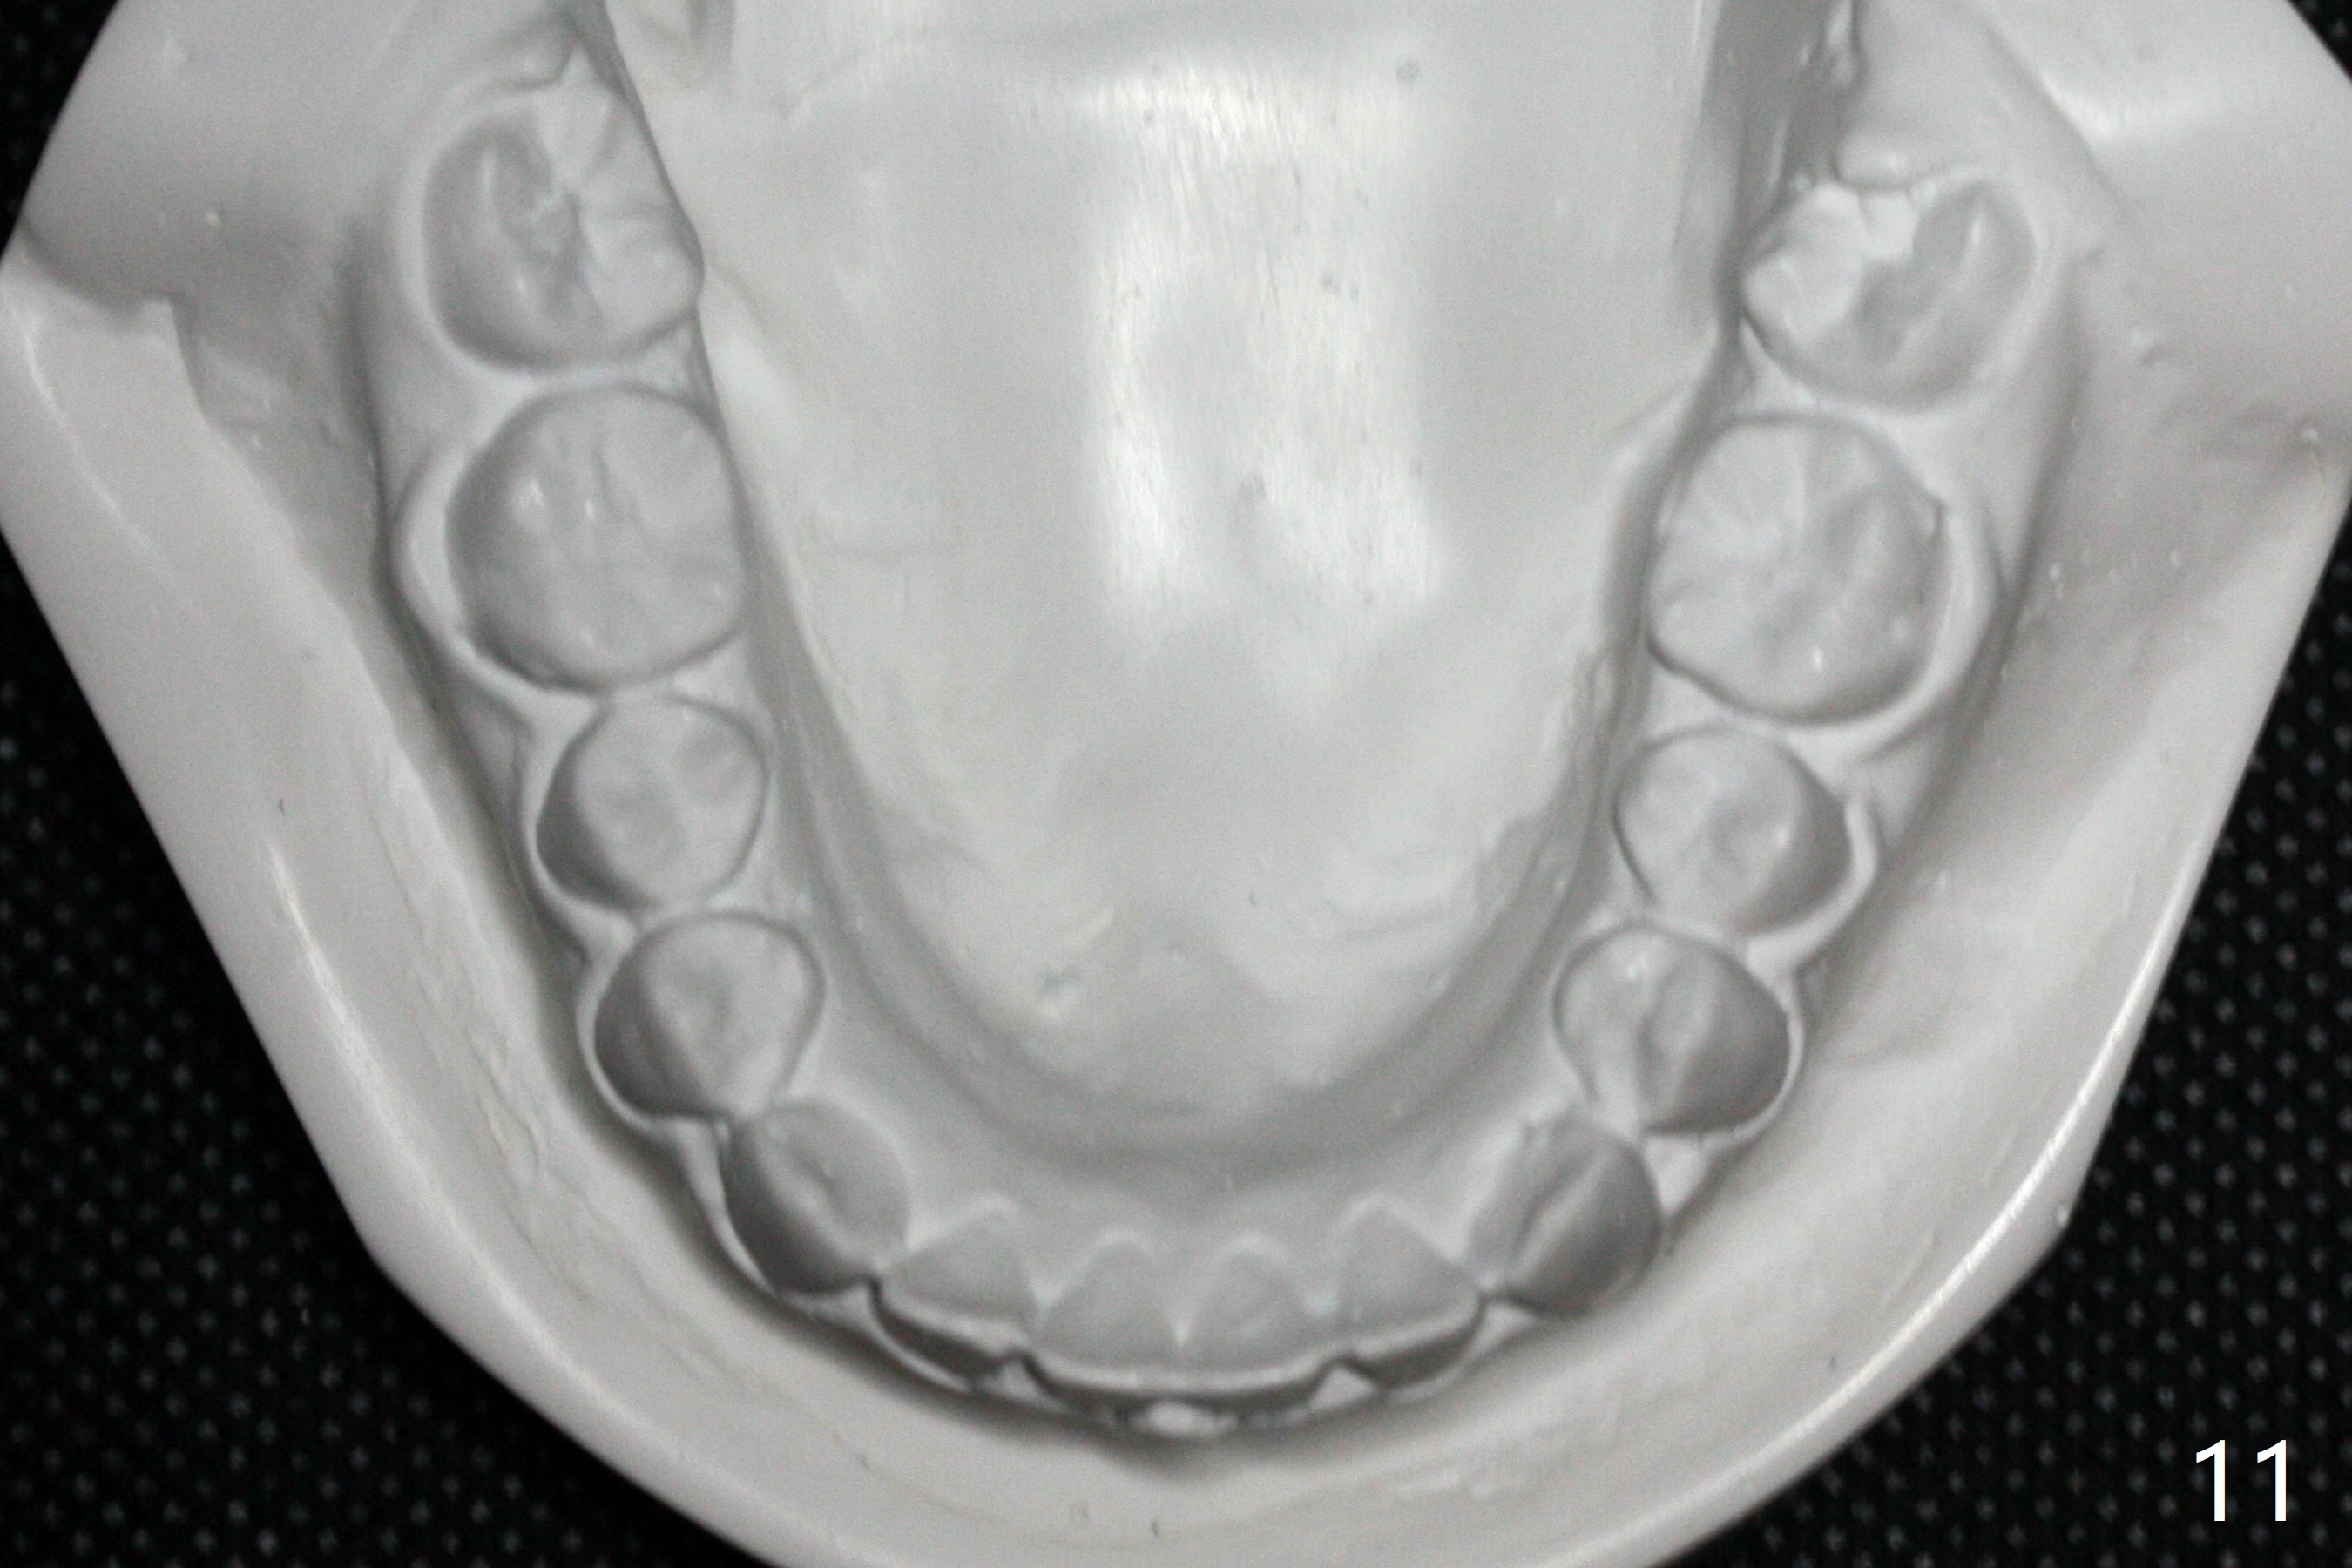

| Pre-op (11 y/o) | Post-op (12 y/o) | Follow Up (14 y/o) |

Relapse

A 11-year-old man starts orthodontic treatment and finishes in 9 months. Two years later crowding relapses because of loss of suck down retainers. It appears that lingual retainer is necessary.